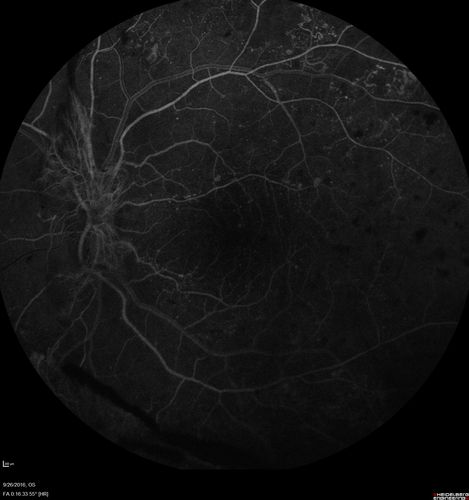

PDR NVD left eye and NVE right eye

41 year old diabetic woman with PDR in both eyes. High risk in the left eye. She had PRP, Avastin, and vitrectomy x 2 in the left eye with final vision of 20/25. The right eye had eventually PRP laser

Proliferative Diabetic Retinopathy NVD left eye and NVE right eye - Ultrawide field FA